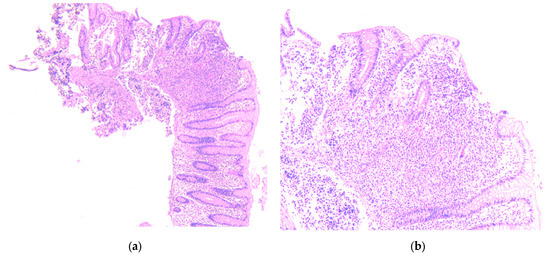

Synchronous Pulmonary and Cecal High-Grade Neuroendocrine Carcinomas Presenting as Hepatic Metastases: A Diagnostic Challenges and Literature Review

Background and Clinical Significance: Neuroendocrine neoplasms (NENs) are a group of malignancies that may remain clinically silent for many years. The presence of hepatic metastases can be the first clue leading to diagnosis. Case Presentation: We report the case of a 67-year-old man [...] Read more.

Background and Clinical Significance: Neuroendocrine neoplasms (NENs) are a group of malignancies that may remain clinically silent for many years. The presence of hepatic metastases can be the first clue leading to diagnosis. Case Presentation: We report the case of a 67-year-old man with intermittent tiredness and suspicious hepatic nodules detected on routine abdominal ultrasound. Contrast-enhanced ultrasonography showed arterial hyperenhancement with early washout, suggestive of metastases. Synchronous high-grade neuroendocrine carcinomas (NECs) of the lung and cecum were identified. Although the liver lesions were initially presumed to arise from the cecal tumor, liver biopsy immunohistochemistry was TTF-1 positive/CDX2 negative, whereas the cecal lesion was TTF-1 negative/CDX2 positive. This mutually exclusive immunophenotype confirmed two separate primary carcinomas. Given the high-grade histology, the patient received platinum-based chemotherapy and achieved a partial response. Conclusions: This case illustrates the diagnostic complexity of synchronous lesions and highlights the “mirage of the first lesion” phenomenon, in which the initially detected tumor may not represent the true primary site. A comprehensive, multidisciplinary strategy is crucial for establishing the correct diagnosis and guiding optimal management. Full article

(This article belongs to the Special Issue Diagnosis and Management of Neuroendocrine Tumors)